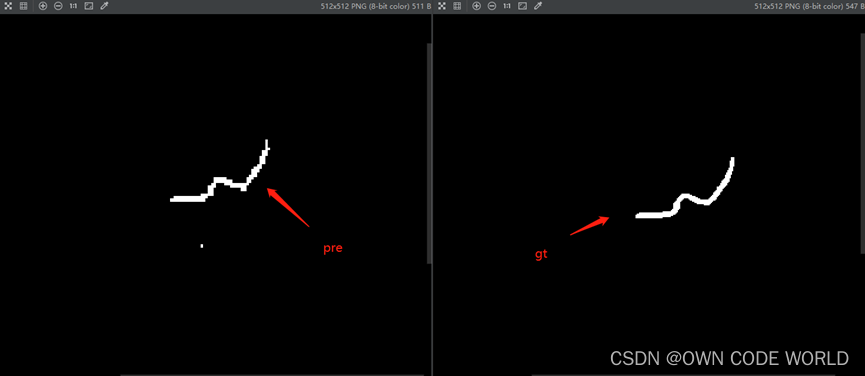

19.由于我们以前使用的模型比如unet,跑出来的结果都是png,但是此为.nii.gz,因此下面时想将.nii.gz转化为png.因此就去查找了相关的代码,并进行了简单的修改。将.nii.gz 转化为了png格式,如下图所示,转化过来的png存在一些问题(Q5:猜测是像素值的区间出现了问题,例如边缘部分的像素值本来是0,但是现在是80.这个问题还未解决)

- 利用转化的gt和pre图像,计算dice、recall、precision结果如下(这里我训练和测试的数据集搞错了,用的是相同的。):